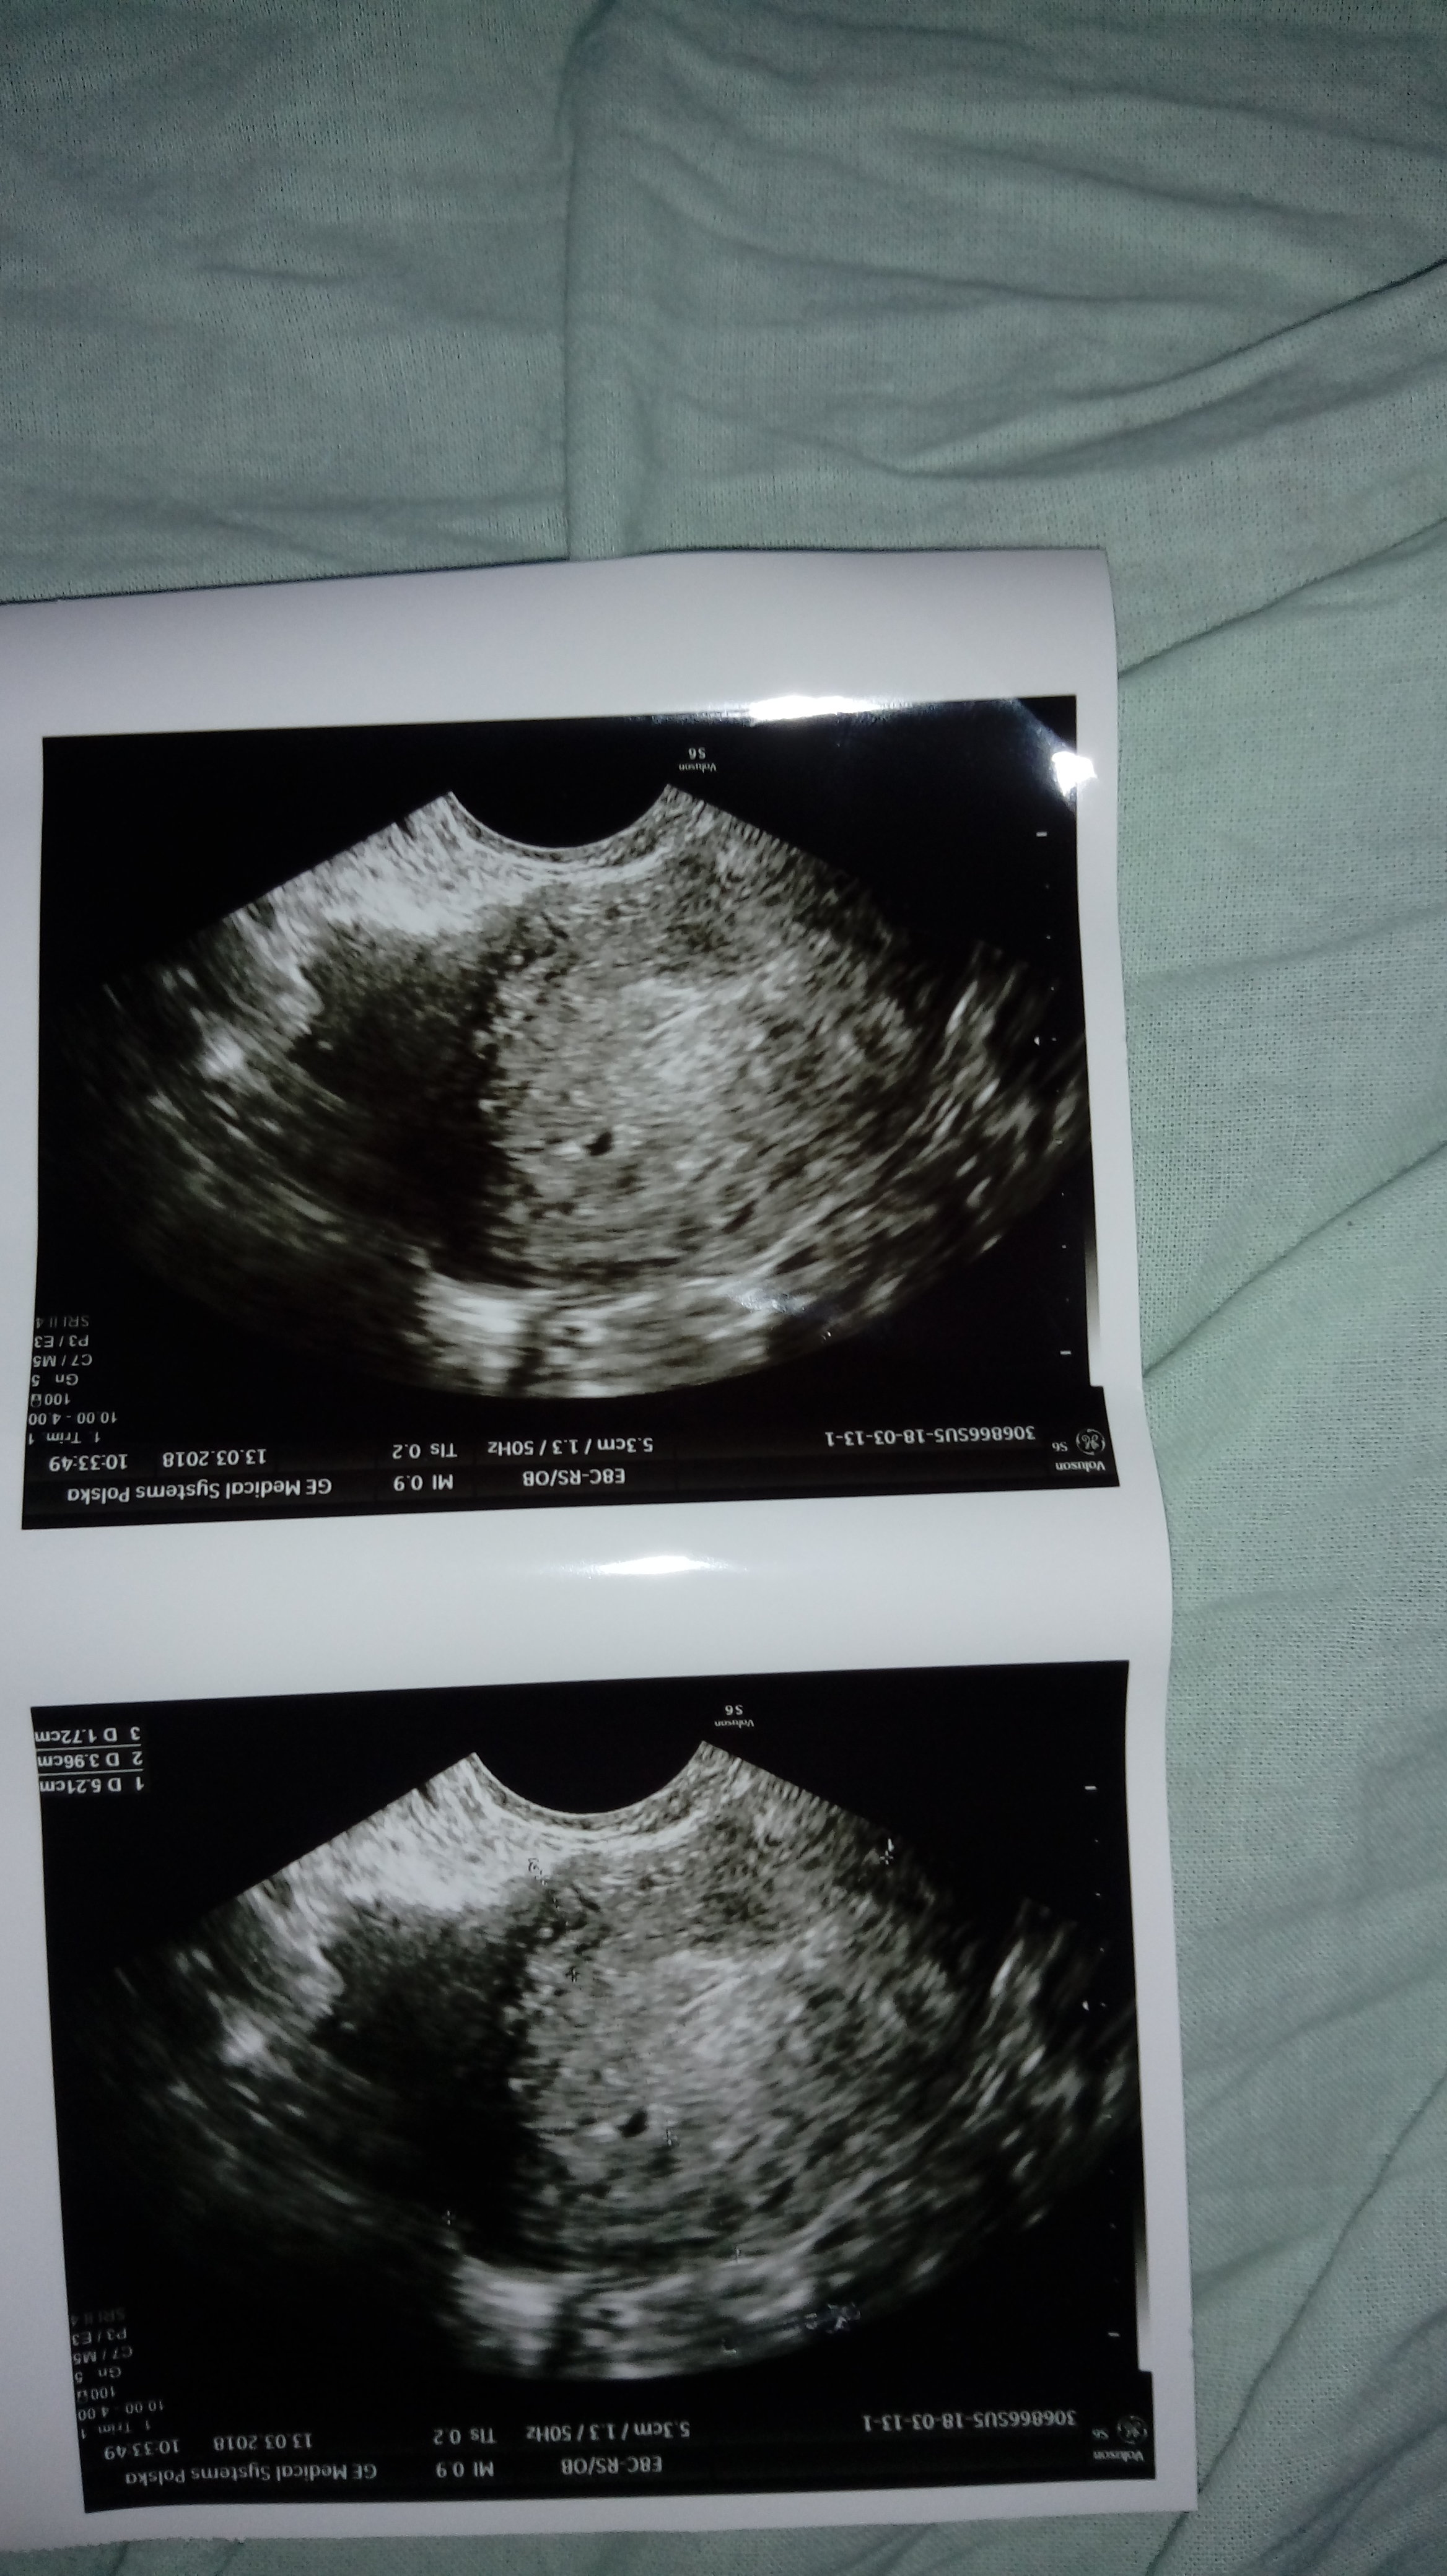

A o świadczy z usg dnia 6 marca : trzon macicy 48x41mm endometrium 13.5mm

a z usg z 13 marca : trzon macicy

52x40mm endometrium 17mm i widoczy pęcherzyki ciążowy prawdopodobnie ???

Źle chyba sie wyraziłam. Gin mi w opisie napisał że : "w obrębie endometrium widoczna niewielka hypoechogeniczna przestrzeń( pęcherzyk ciążowy?)"

To jest ciąża na 1000%. Nawet blada kreska na teście potwierdza. A opis USG jest tylko potwierdzeniem że test się nie pomylił - na tym etapie to że cokolwiek widać to i tak dużo - a ginekolodzy zawsze są zachowawczy bo na tym etapie często zdarza się poronienie i wolą kobiet nie nakręcać. A endometrium 17 to dodatkowo przesłanka. A jak masz jeszcze wątpliwości to zrób betę - zobaczysz że wyjdzie wysoka.

To moje dzisiejsze usg. A bete robie jutro;)